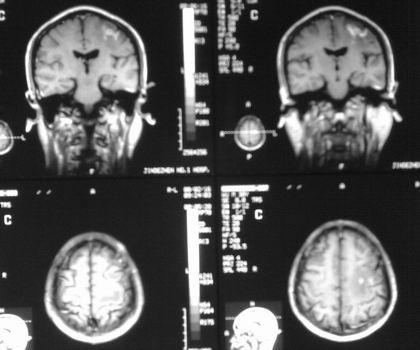

以下是引用杀毒软件在2008-2-17 14:43:00的发言:[br]左顶叶见片状低密度影,内见点状影,占位效应不明显。[br]左顶叶结核性肉芽肿可能性大。脑囊虫病?做补体结合试验除外。